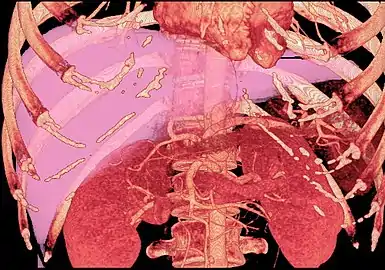

Technique

Before transplantation, liver-support therapy might be indicated (bridging-to-transplantation). Artificial liver support like liver dialysis or bioartificial liver support concepts are currently under preclinical and clinical evaluation. Virtually all liver transplants are done in an orthotopic fashion; that is, the native liver is removed and the new liver is placed in the same anatomic location.[7] The transplant operation can be conceptualized as consisting of the hepatectomy (liver removal) phase, the anhepatic (no liver) phase, and the postimplantation phase. The operation is done through a large incision in the upper abdomen. The hepatectomy involves division of all ligamentous attachments to the liver, as well as the common bile duct, hepatic artery, hepatic vein and portal vein. Usually, the retrohepatic portion of the inferior vena cava is removed along with the liver, although an alternative technique preserves the recipient's vena cava ("piggyback" technique).

The donor's blood in the liver will be replaced by an ice-cold organ storage solution, such as UW (Viaspan) or HTK, until the allograft liver is implanted. Implantation involves anastomoses (connections) of the inferior vena cava, portal vein, and hepatic artery. After blood flow is restored to the new liver, the biliary (bile duct) anastomosis is constructed, either to the recipient's own bile duct or to the small intestine. The surgery usually takes between five and six hours, but may be longer or shorter due to the difficulty of the operation and the experience of the surgeon.